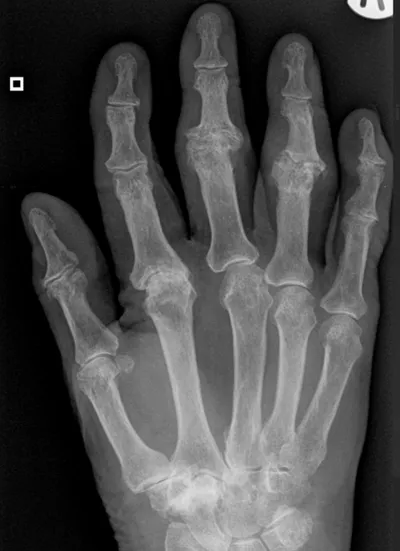

Erosion Radiology Images

This collection contains 1 radiology images related to erosion, including various imaging modalities such as X-rays, MRIs, CT scans, and ultrasound images commonly used in medical diagnosis and education.